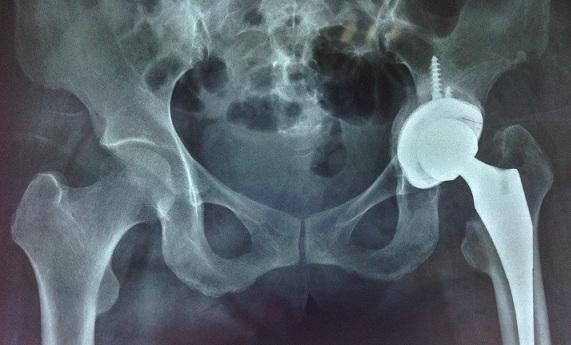

关节置换手术,对于终末期关节病变的很多患者,很多时候是最后一步了。

但手术后并非就可以高枕无忧了,假体松动、人工关节假体周围感染等都可能导致远期手术的失败。

而大部分的此类病人当中,绝大部分的患者可能需要再次手术(二进宫),取出第一次手术的关节假体,重新使用一套新的人工关节......